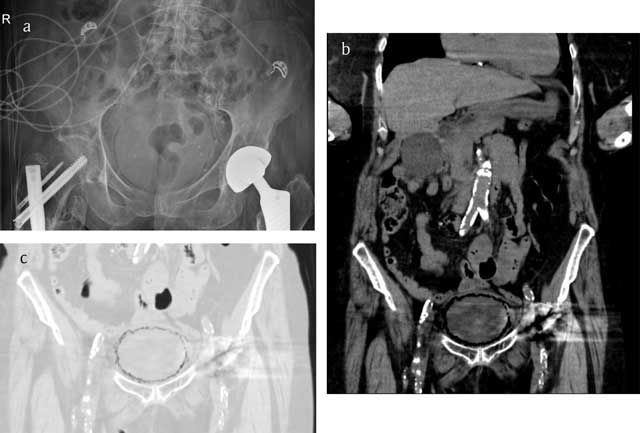

Figure 1

Conventional radiograph (a) in a case of emphysematous cystitis shows sharply demarcated, curvilinear areas of increased lucency in the pelvis. Computed tomography (b, c) images more clearly reflect the cobblestone aspect of intramural gas delineating the bladder wall, often likened to a “beaded necklace” appearance.